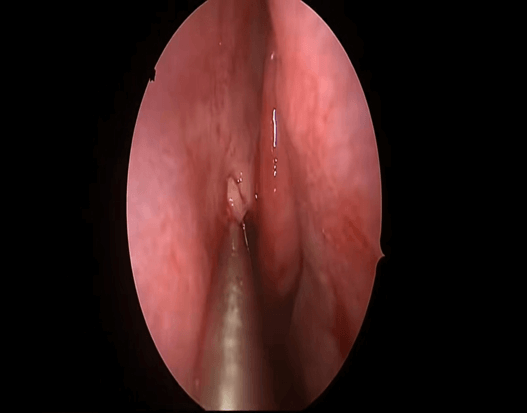

鼻息肉是耳鼻喉科常见病症之一,与部分全身性疾病也存在关联。它本质上是鼻黏膜长期受炎症刺激导致组织水肿、逐渐下垂形成的良性肿物。外观多呈灰白、淡黄或淡红色,形似荔枝肉,表面光滑,半透明,多发生于中鼻道、窦口及筛窦区域,严重时可堵塞鼻腔,影响呼吸与嗅觉。

•鼻内镜下鼻内病损微创切除术:适用于鼻腔鼻窦多发息肉。该术式借助鼻内窥镜精细操作,能充分开放窦腔、彻底摘除息肉。我院近年来开展的鼻内镜微创手术,具有精细、准确、创伤小、恢复快的优势,能显著降低术后复发率。